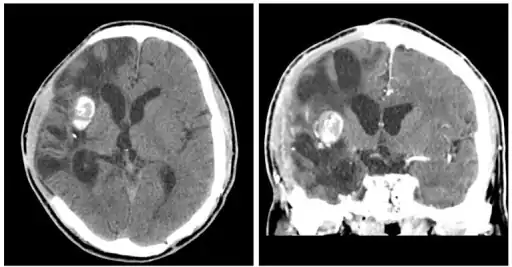

CT scans show calcified brain abscess. -

The diagnosis is established by a computed tomography (CT) (with contrast) examination. At the initial phase of the inflammation (which is referred to as cerebritis), the immature lesion does not have a capsule and it may be difficult to distinguish it from other space-occupying lesions or infarcts of the brain. Within 4–5 days the inflammation and the concomitant dead brain tissue are surrounded with a capsule, which gives the lesion the famous ring-enhancing lesion appearance on CT examination with contrast (since intravenously applied contrast material can not pass through the capsule, it is collected around the lesion and looks as a ring surrounding the relatively dark lesion). Lumbar puncture procedure, which is performed in many infectious disorders of the central nervous system is contraindicated in this condition (as it is in all space-occupying lesions of the brain) because removing a certain portion of the cerebrospinal fluid may alter the concrete intracranial pressure balances and causes the brain tissue to move across structures within the skull (brain herniation).

Ring enhancement may also be observed in cerebral hemorrhages (bleeding) and some brain tumors. However, in the presence of the rapidly progressive course with fever, focal neurologic findings (hemiparesis, aphasia etc.) and signs of increased intracranial pressure, the most likely diagnosis should be the brain abscess.